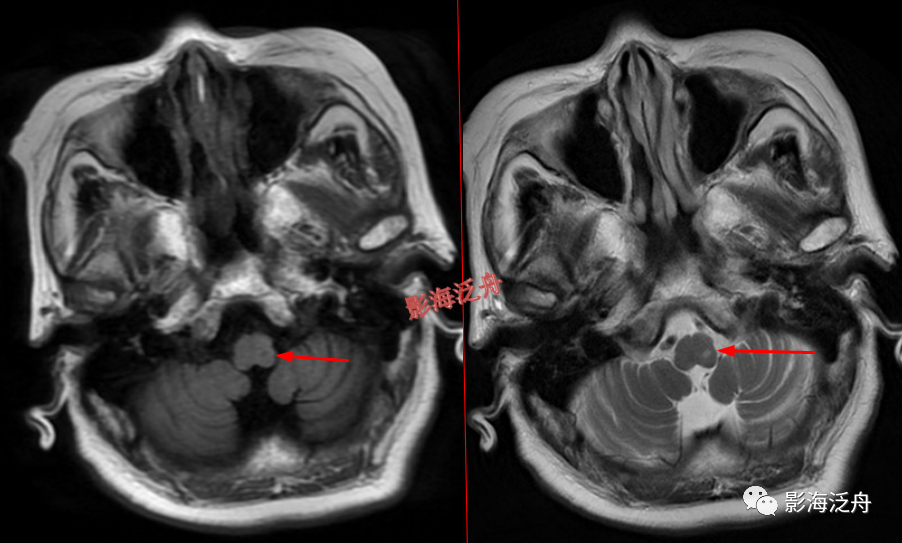

颅骨病变

左侧岩尖部囊性病变(红箭头),患者未术,病理不明。MR对骨质结构显示不佳,因此很多读者会忽略掉颅内骨质病变的观察,很多颅内病变,如三叉神经鞘瘤、鼻咽癌

等都会造成颞骨岩部(红色标注区)骨质破坏,因此,平时应对此处多加留意。黄箭头指听神经及内耳结构。

蝶骨骨纤维异常增殖症(红箭头),病灶内部可见特征性的囊变区(黄箭)。蝶骨的病变在MR上识别起来更为困难,因为蝶骨位于颅底部,此处骨骼、肌肉、脂肪等多种组织成分混杂,导致正常情况下也看起来非常乱。不要着急,慢慢学。

左侧顶骨骨纤维异常增殖症。病灶位于左侧顶骨板障区,局部骨质呈膨胀性改变,病灶边缘骨质硬化,呈明显低信号(红箭头),内部可见大片状絮状结构(黄箭)以及局灶性的玻璃样变性区(绿箭头)。